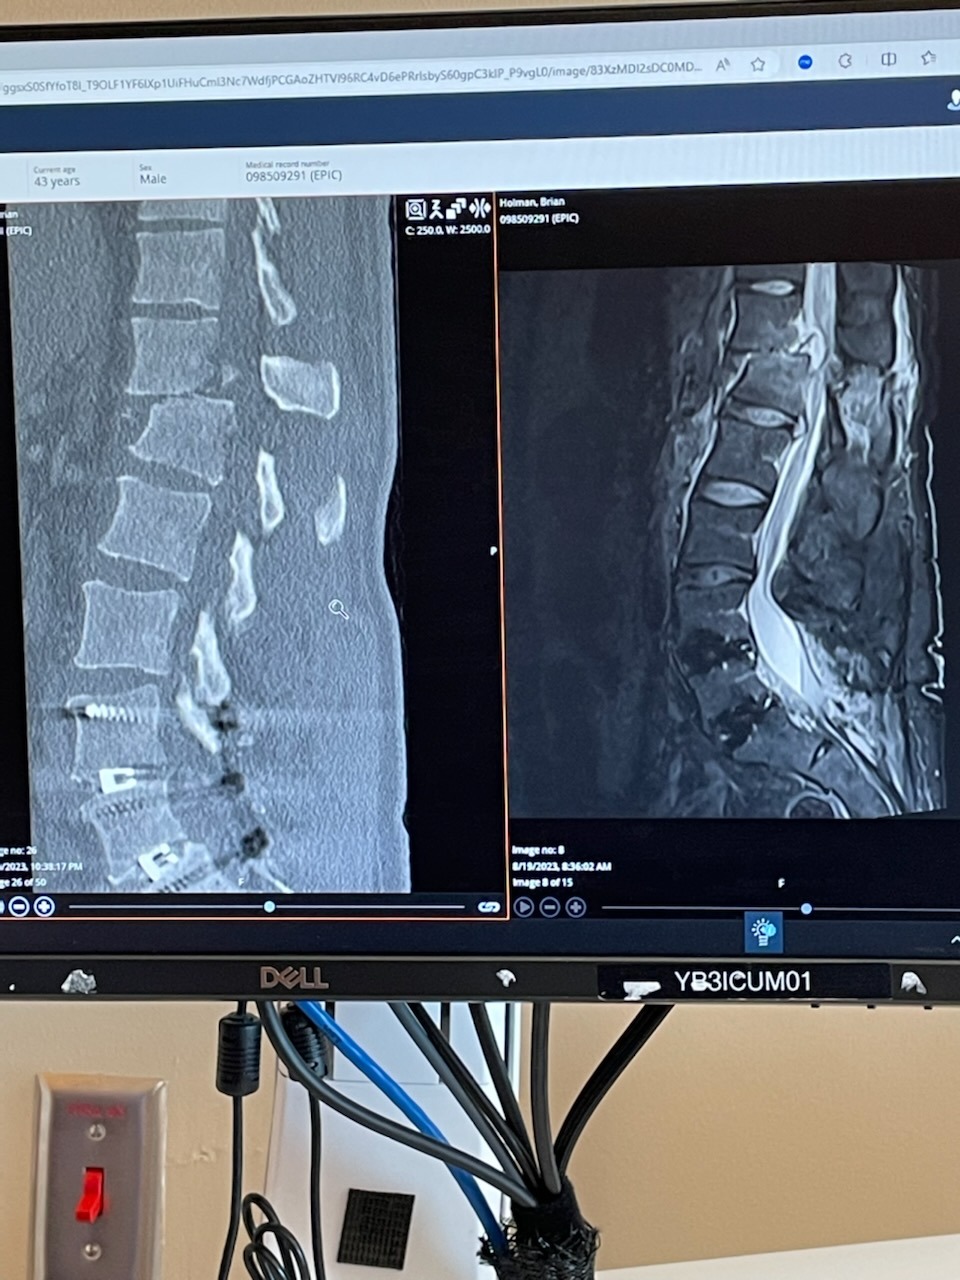

On August 18th, 2023, I had gone to town for a part to complete a small wood project, and as I was going through the green light, a 17-year-old turned into and over my motorcycle. I was airlifted with a broken back, paralyzed, and missing my left leg after amputation, five broken ribs, a plate on my broken collarbone, and road rash. I've had five surgeries just within weeks of the accident. The teenager driving had been on the phone during the accident and afterward didn't even call 911. Later, we found out that she had been driving as a restricted driver under their insurance policy, so no insurance, and I only had liability.